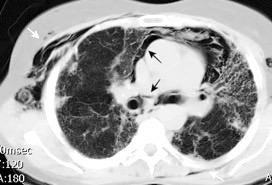

Diafragma “colgante” (“dangling sign”)

(“Dangling sign”)

TC. Mejor con multicorte. (reconstrucciones).

Asociación: Aire en pared.

Fracturas costal .Rotura esplénica. Neumoperitoneo.

Diafragma discontinúo Herniación de la grasa omental

Desser TS et al.The dangling diaphragm sign: sensitivity and comparison with existing CT signs of blunt traumatic diaphragmatic rupture. Emerg Radiol 2010